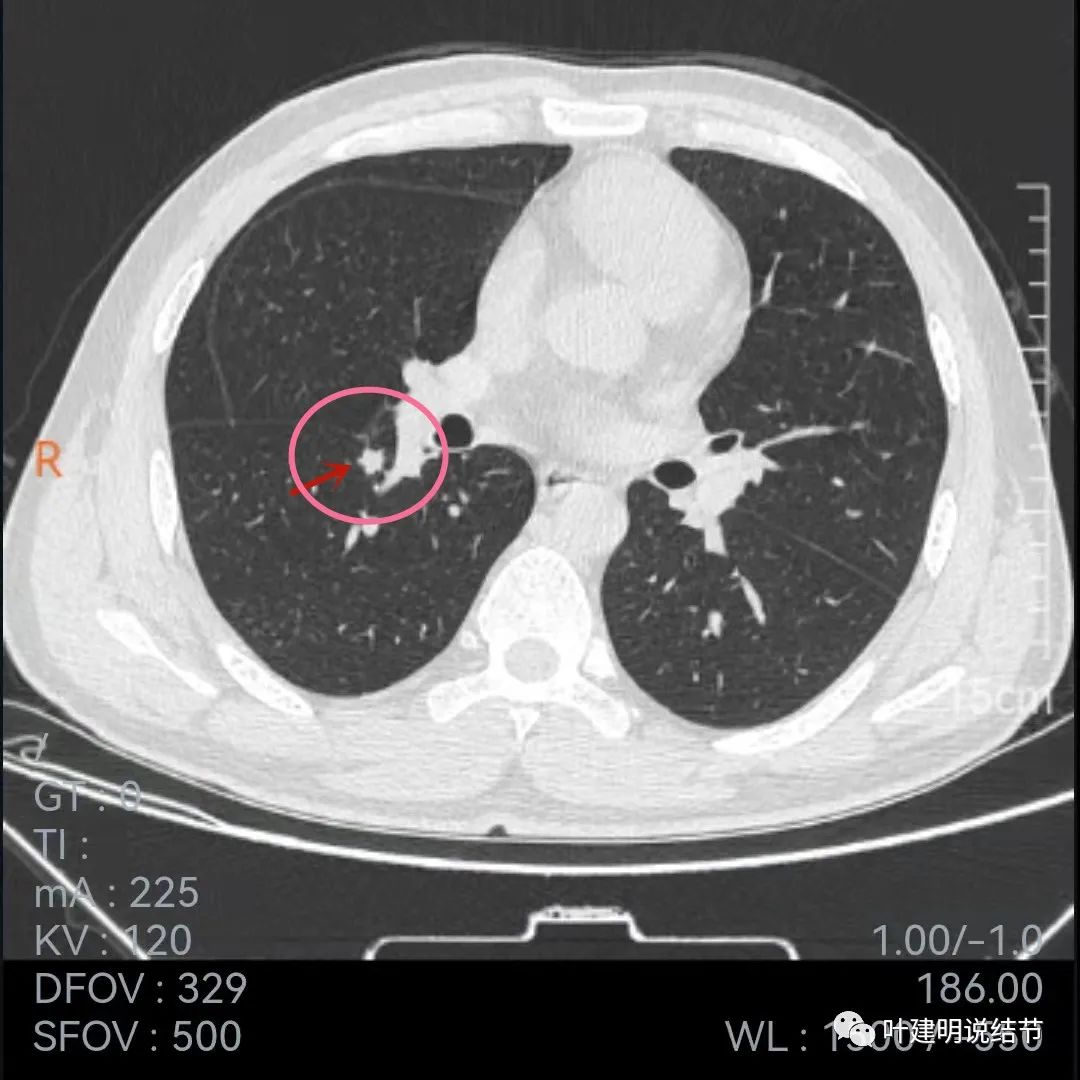

再看今年9月份的平扫片子:

也是三个层面可见,较去年也许略有增大,但测量起来可能差别不大,因为也是6-7毫米许。